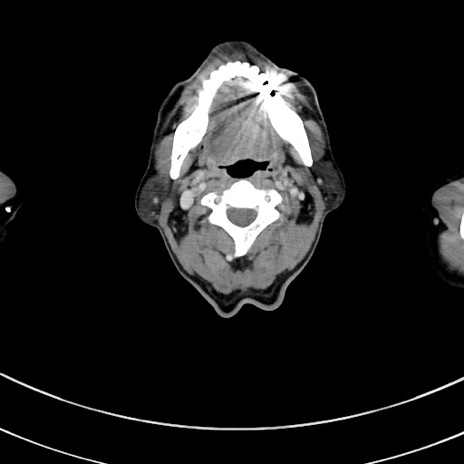

症例8(横断像)

【症例】 60歳代男性

【主訴】 黒色吐物

【現病歴】 4日前から嘔気自覚、2日前の朝食後にも嘔気あり、自分で手で嘔吐反射起こし嘔吐したところ血が混ざっていたため受診。

【既往歴】 5年前汎発性腹膜炎を伴う急性虫垂炎で手術、高血圧、前立腺肥大症、高脂血症

【身体所見】 腹部正中に手術癩痕あり 腹部平坦・軟圧痛なし膨満感あり

【データ】WBC 8400、CRP 4.54